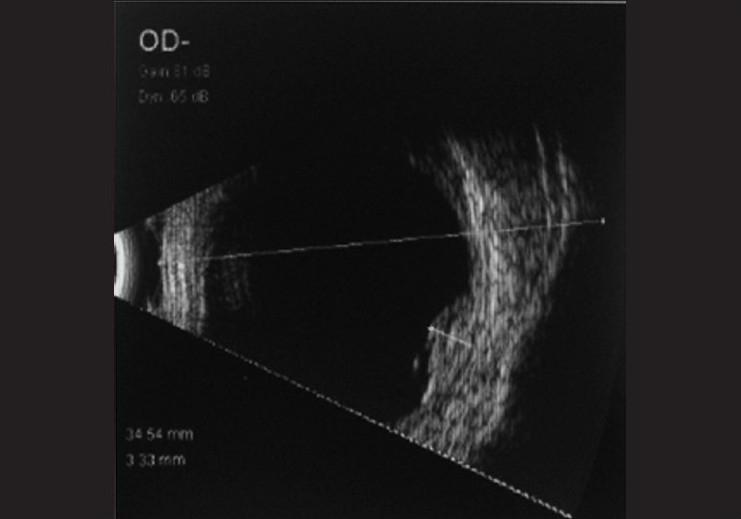

与未经治疗的脉络膜黑色素瘤相关的视网膜下脂质渗出。

Subretinal lipid exudation associated with untreated choroidal melanoma.

Subretinal lipid exudation in an untreated choroidal melanoma is very rare. It is seen following plaque radiotherapy in choroidal melanoma. There is only one case report of untreated choroidal melanoma with massive lipid exudation in a patient with metastatic hypernephroma. We report here a rare case of untreated choroidal melanoma with lipid exudation. Subretinal exudation that is rarely seen following plaque brachytherapy was noted at the borders of this untreated tumor. Lipid exudation partially resolved following brachytherapy.

摘要

未经治疗的脉络膜黑色素瘤很少出现视网膜下脂质渗出。这种情况见于脉络膜黑色素瘤的放射性敷贴治疗后。仅有一例转移性肾细胞瘤患者的未经治疗的脉络膜黑色素瘤伴大量脂质渗出的病例报告。我们在此报告一例罕见的未经治疗的脉络膜黑色素瘤伴脂质渗出的病例。在该未经治疗的肿瘤边缘观察到放射性敷贴治疗后罕见的视网膜下渗出。脂质渗出在放射性敷贴治疗后部分缓解。